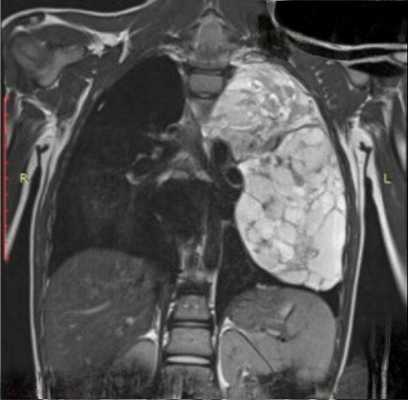

Верификация рака вилочковой железы основана на использовании высокоинформативных методов диагностики, среди которых основное место принадлежит компьютерной и магнитно-резонансной томографии. Для уточнения гистологической структуры новообразования возможно выполнение медиастиноскопии с применением эндовидеотехники. Выявление метастазов рака тимуса в другие органы возможно с помощью сцинтиграфии с применением тропных к опухоли радиофармпрепаратов.

На рентгенограмме грудной клетки тимома имеет вид объемного образования неправильной формы, расположенного в переднем средостении. КТ грудной клетки значительно расширяет объем информации, полученный при первичной рентгендиагностике и в ряде случаев позволяет поставить морфологический диагноз. Уточнение локализации и взаимоотношения новообразования с соседними органами при КТ средостения позволяет в дальнейшем выполнить трансторакальную пункцию опухоли средостения, что чрезвычайно важно для гистологического подтверждения диагноза и верификации гистологического типа тимомы.

Компьютерная томография с контрастированием — более информативный метод. Он позволяет получить информацию о наличии новообразования, определить его злокачественность, и даже дифференцировать его природу — отличить тимому от лимфомы и др. МРТ не является рутинным методом диагностики тимом, но может использоваться по показаниям, например, при наличии у пациента аллергии на йодсодержащий контраст, применяемый при КТ.